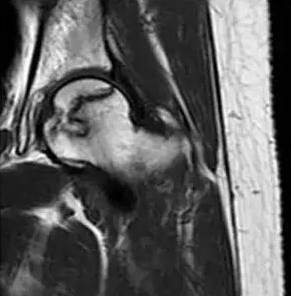

在股骨头坏死极早期,磁共振即可捕捉到特征性带状低信号、双线征等典型表现,比其他检查提前数月甚至一年发现问题,为保髋治疗赢得黄金时间。中晚期则能明确股骨头是否塌陷、关节受损程度,帮助医生制定科学治疗方案。

(T1加权像的带状低信号带)